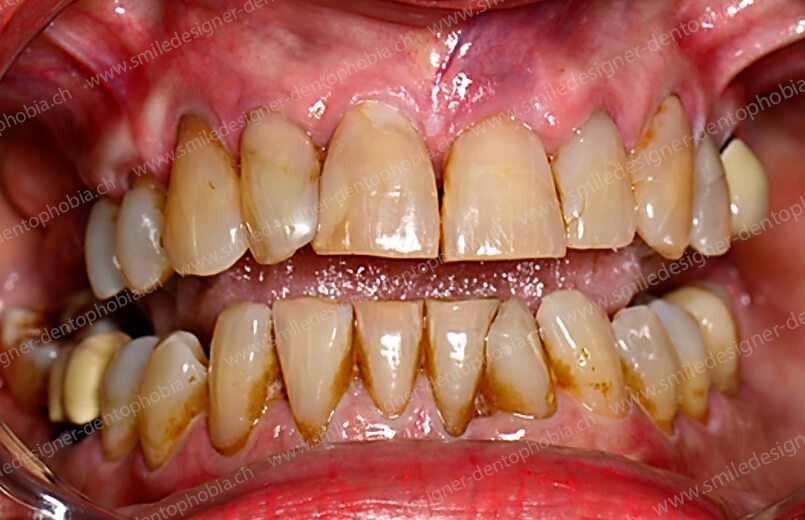

Cas clinique « GOLD STANDARD MCI » bi-maxillaire : Bridge implanto-porté sans extension postérieure (ALL ON 10). Version définitive des bridges avec un cosmétique en céramique.

Cas clinique « GOLD STANDARD MCI » bi-maxillaire : Bridge implanto-porté sans extension (ALL ON 8) au maxillaire et à la mandibule. Version définitive des bridges avec un cosmétique en céramique.